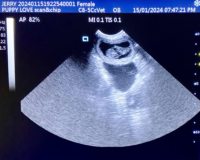

Mobile Ultrasound Pregnancy Scanning and Microchipping Services

Puppy Love scan and chip